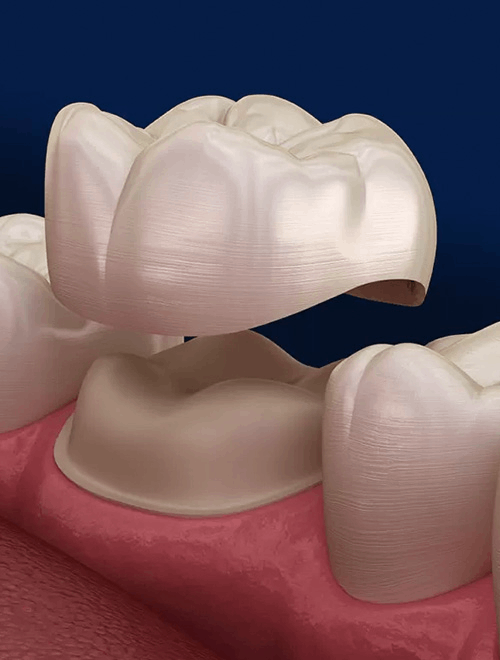

CEREC - same day crown

CEREC (Chairside Economical Restoration of Esthetic Ceramics) is a CAD/CAM technology that allows dentists to design, create, and place a custom, high-quality ceramic crown in a single appointment. It eliminates the need for messy traditional impressions, temporary crowns, and second visits by milling the restoration on-site in under two hours